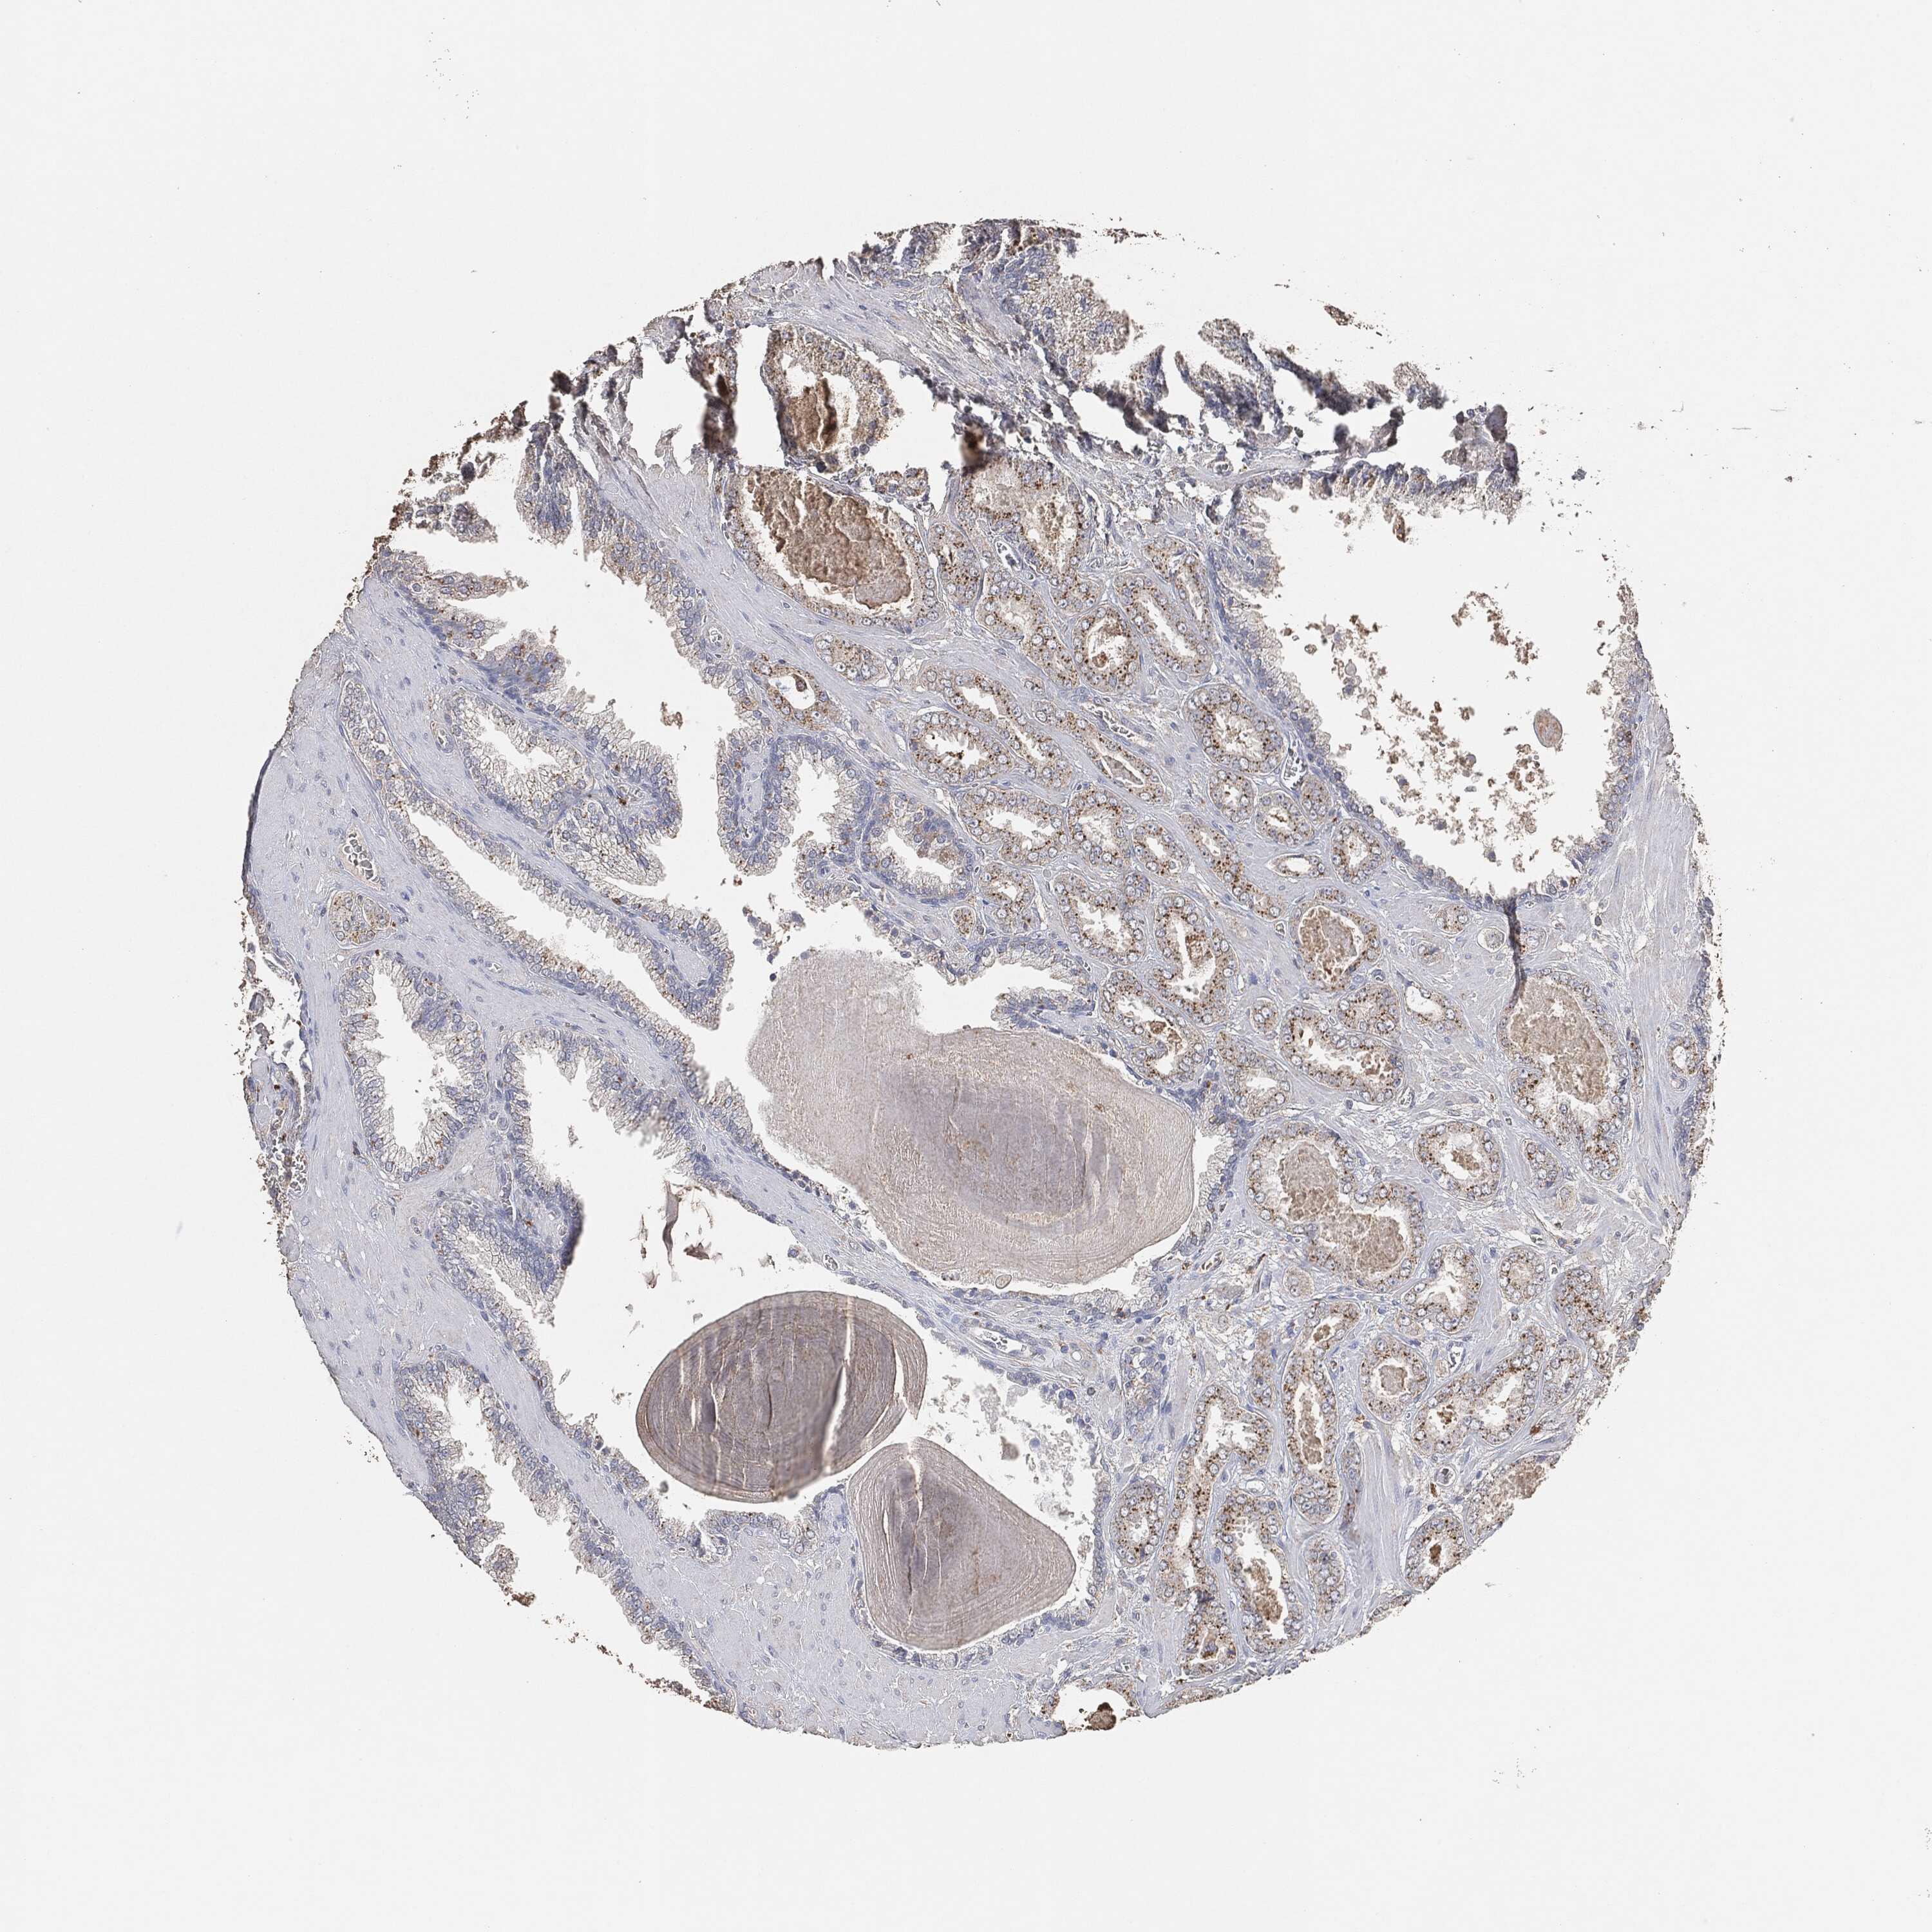

PROSTATE CANCER - Protein expressioni

A mouse-over function shows sample information and annotation data. Click on an image to view it in a full screen mode. Samples can be filtered based on level of antibody staining by selecting one or several of the following categories: high, medium, low and not detected. The assay and annotation is described here.

Note that samples used for immunohistochemistry by the Human Protein Atlas do not correspond to samples in the TCGA dataset.

Antibody stainingi

Antibody staining in the annotated cell types in the current human tissue is reported as not detected, low, medium, or high, based on conventional immunohistochemistry profiling in selected tissues. This score is based on the combination of the staining intensity and fraction of stained cells.

Each image is clickable and will lead to virtual microscopy that enables deeper exploration of all samples and also displays staining intensity scores, fraction scores and subcellular localization as well as patient and tissue information for each sample.

Adenocarcinoma, Medium grade

Adenocarcinoma, Low grade

Adenocarcinoma, High grade

Adenocarcinoma, NOS